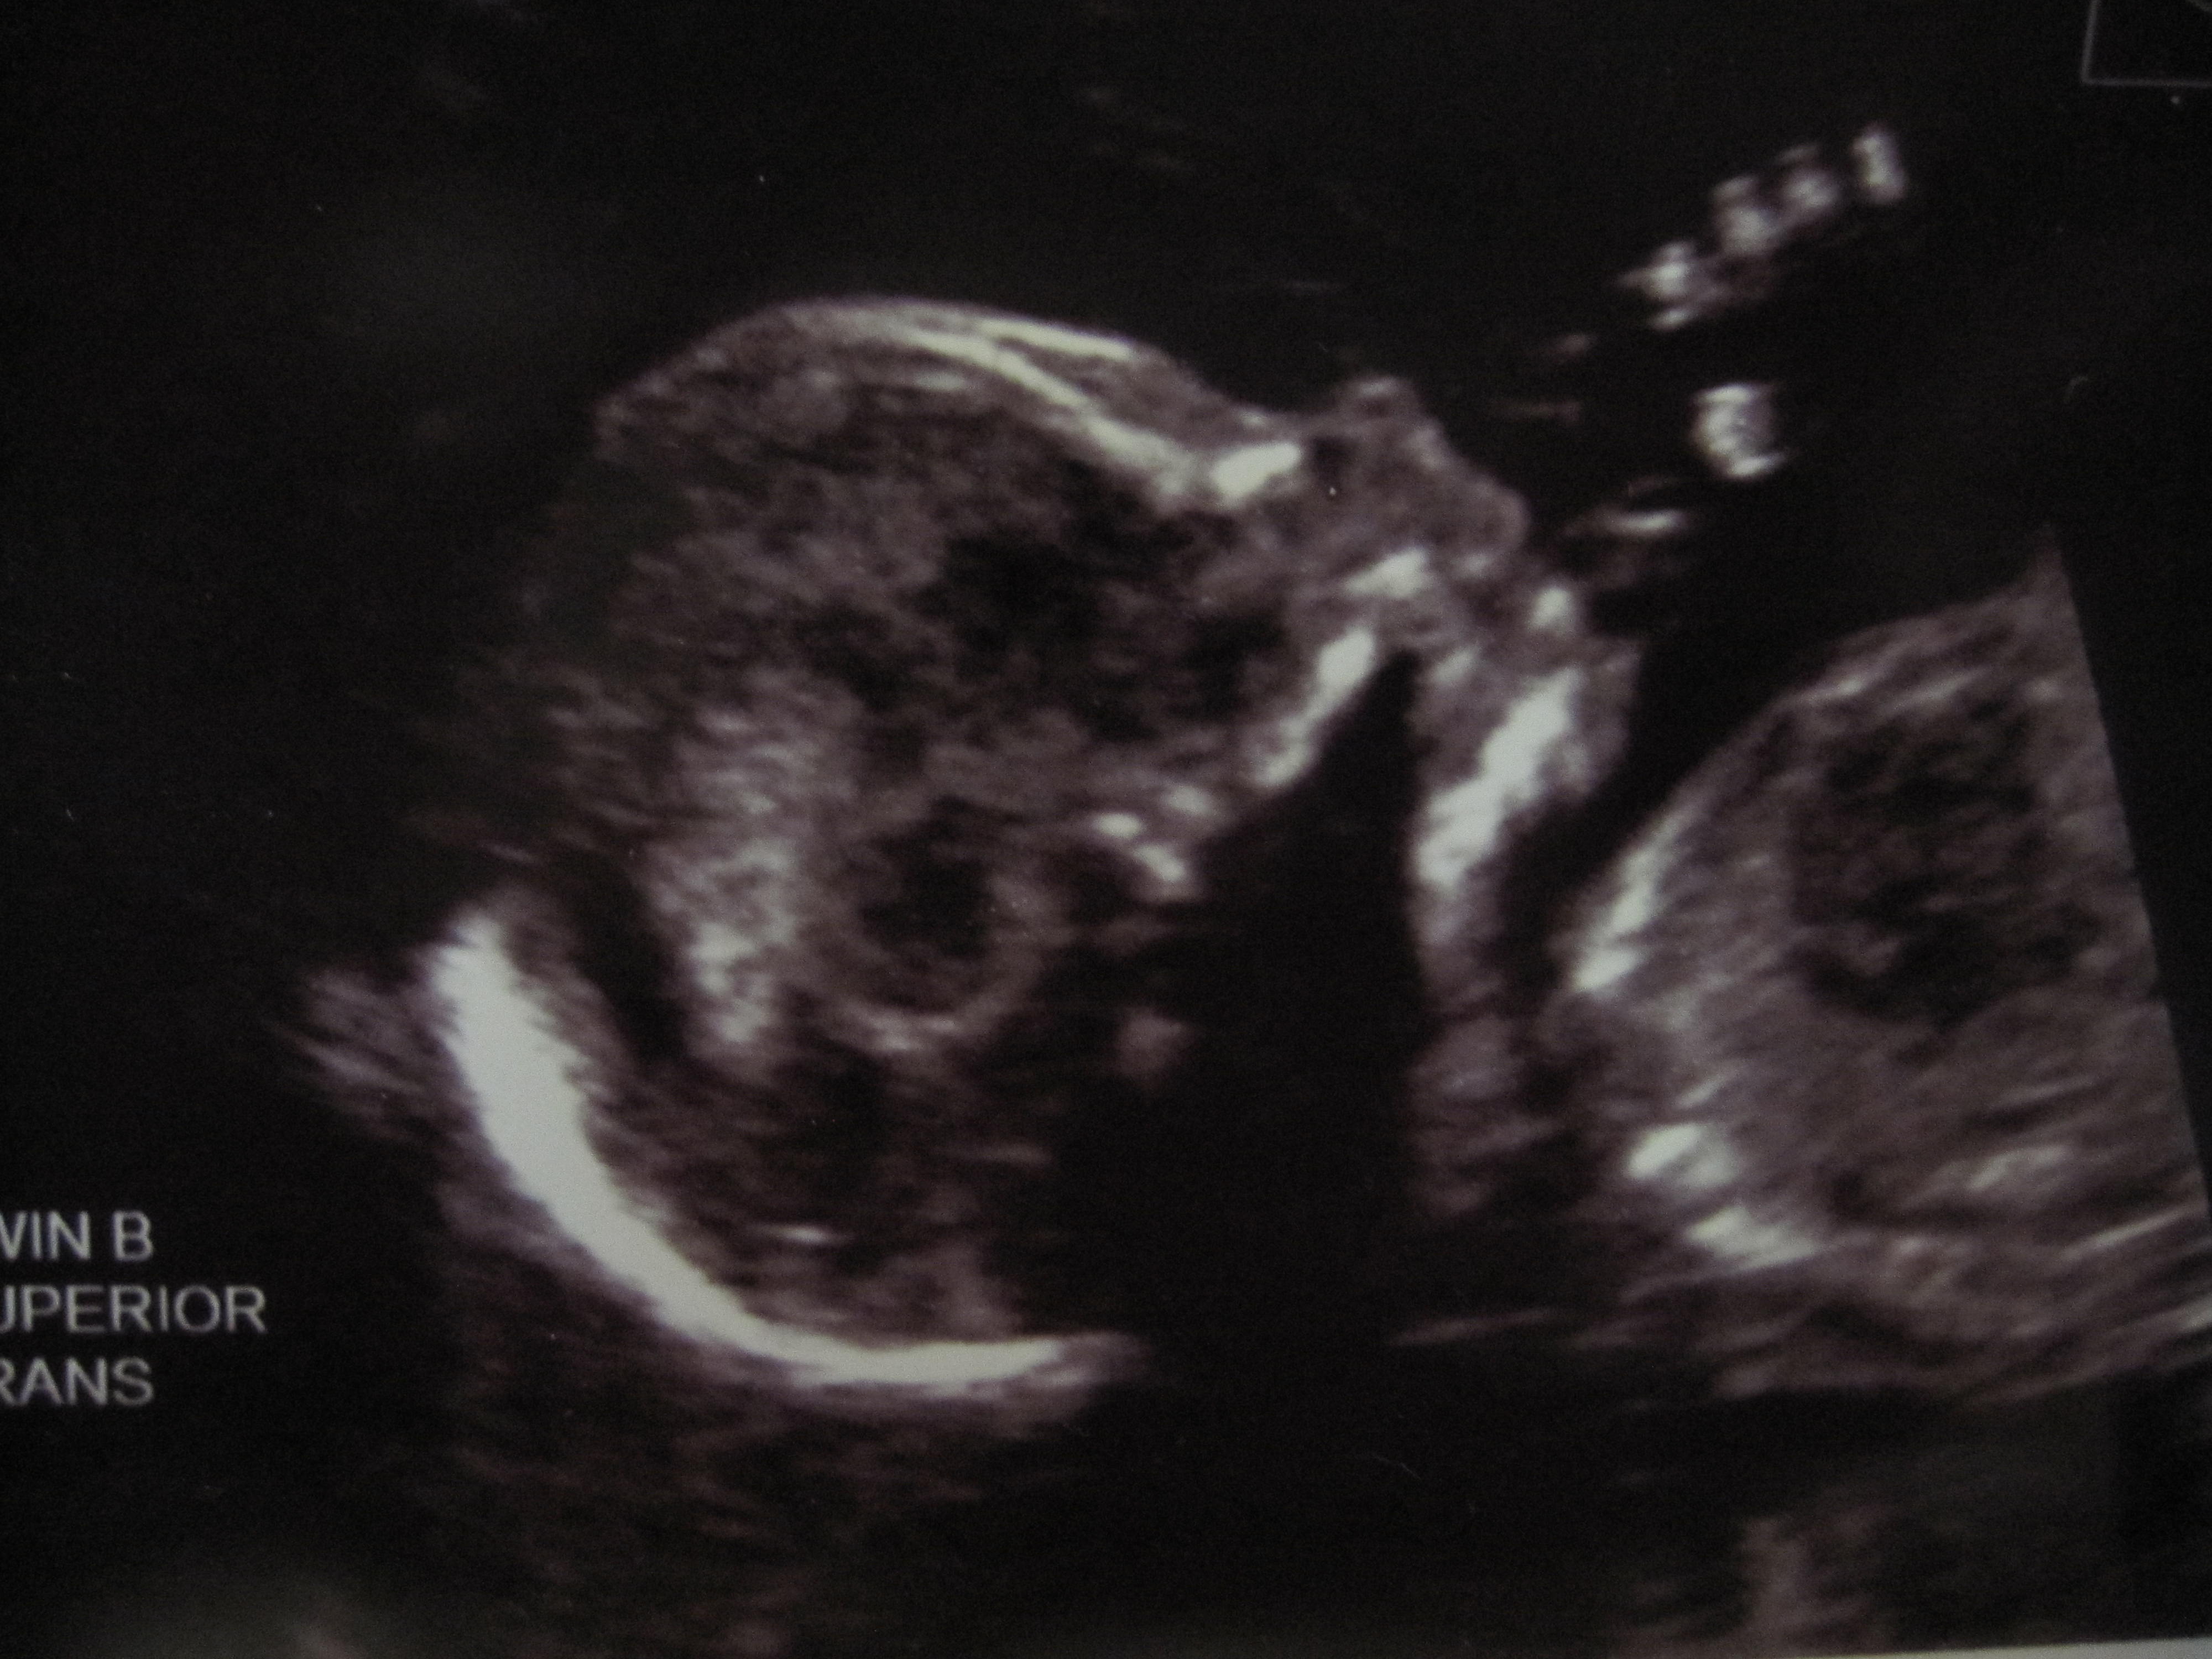

If you look closely, you can see she is smiling. (Baby B, 18wks)

Baby A at 18wks. Looking closely here you can see the umbilical chord. So cool.